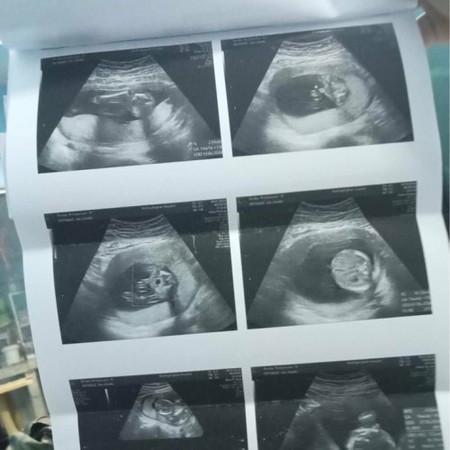

น้องปากแหว่งไหมใครดูออกบ้างดูให้หน่อยค่ะกังวลมาก😭

เราไม่รู้ตัวว่าท้องยัน4เดือนสูบบุหรี่ตลอดดูออกไหมคะว่าน้องปากแหว่งไหม

แนะนำให้ไปซาวด์ 4 มิติ นะค่ะ แต่จะเห็นชัดตอน 28 สัปดาห์ ขึ้นไปค่ะ

แจ้งหมอค่ะ ให้หมอดูให้ ในภาพไม่มีภาพปากน้องค่ะ